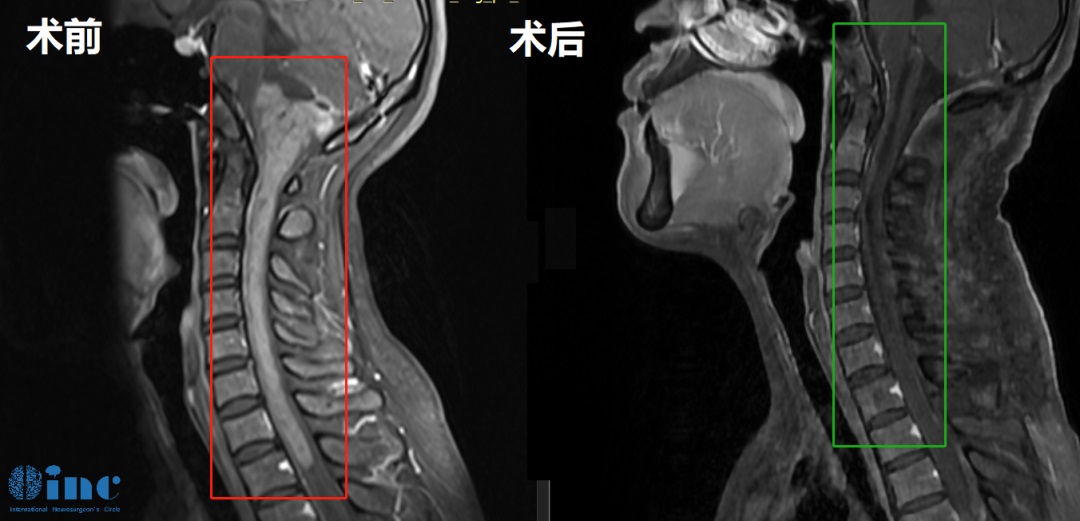

2、14岁男孩-脑干神经节细胞胶质瘤

◉手术日期: 2022年11月巴教授疑难示范手术期间

◉患者情况:14岁的睿睿2016年底偶发左手抓握力弱,2017年初查出神经节细胞瘤;医生表示肿瘤生长缓慢,无法全切,还会复发,故保守观察。后两年病灶缓慢增大,运动能力减弱。2021年底,双侧肢体无力加重,左侧更明显。2022年睿睿再次就医检查,MRI显示桥脑+左侧小脑+颈3以上不规则信号,然而由于肿瘤位于脑干延申至脊髓,肿瘤占位大小33*42*94mm。在国内某医院做了一开始开颅手术,虽仍有不少残留,但手术取得完整病理,肿瘤导致的病情有适当好转,为后续手术提供了清晰的思路、争取了时间……

◉治疗经过:2022年巴教授中国疑难示范手术期间,睿睿父母咨询巴教授能否为孩子顺利手术,“我之前找的主刀医生也都......但教授明确的告诉你最大的风险在于四肢瘫痪,同时他明确的告知全瘫痪的风险是1%。“ ,2022年11月16日,在苏州大学附属儿童医院,巴教授为睿睿进行了手术,全程呼吸、心跳平稳,手术顺利,无新发后遗症。术后2天顺利转出ICU。

◉术后情况:术后11天,巴教授查房时,睿睿已经可以在父母的搀扶下站起来。当教授询问睿睿,“吞咽怎么样?”时,睿睿也能够亲自回答“可以……”!看到孩子睿睿的这么好,巴教授不由得竖起大拇指点赞“Very Good!”

由于睿睿的病程很长,爸爸为了更好的照顾孩子,一直学习护理。苏附儿医生都说睿睿爸爸的护理水平超过很多护士